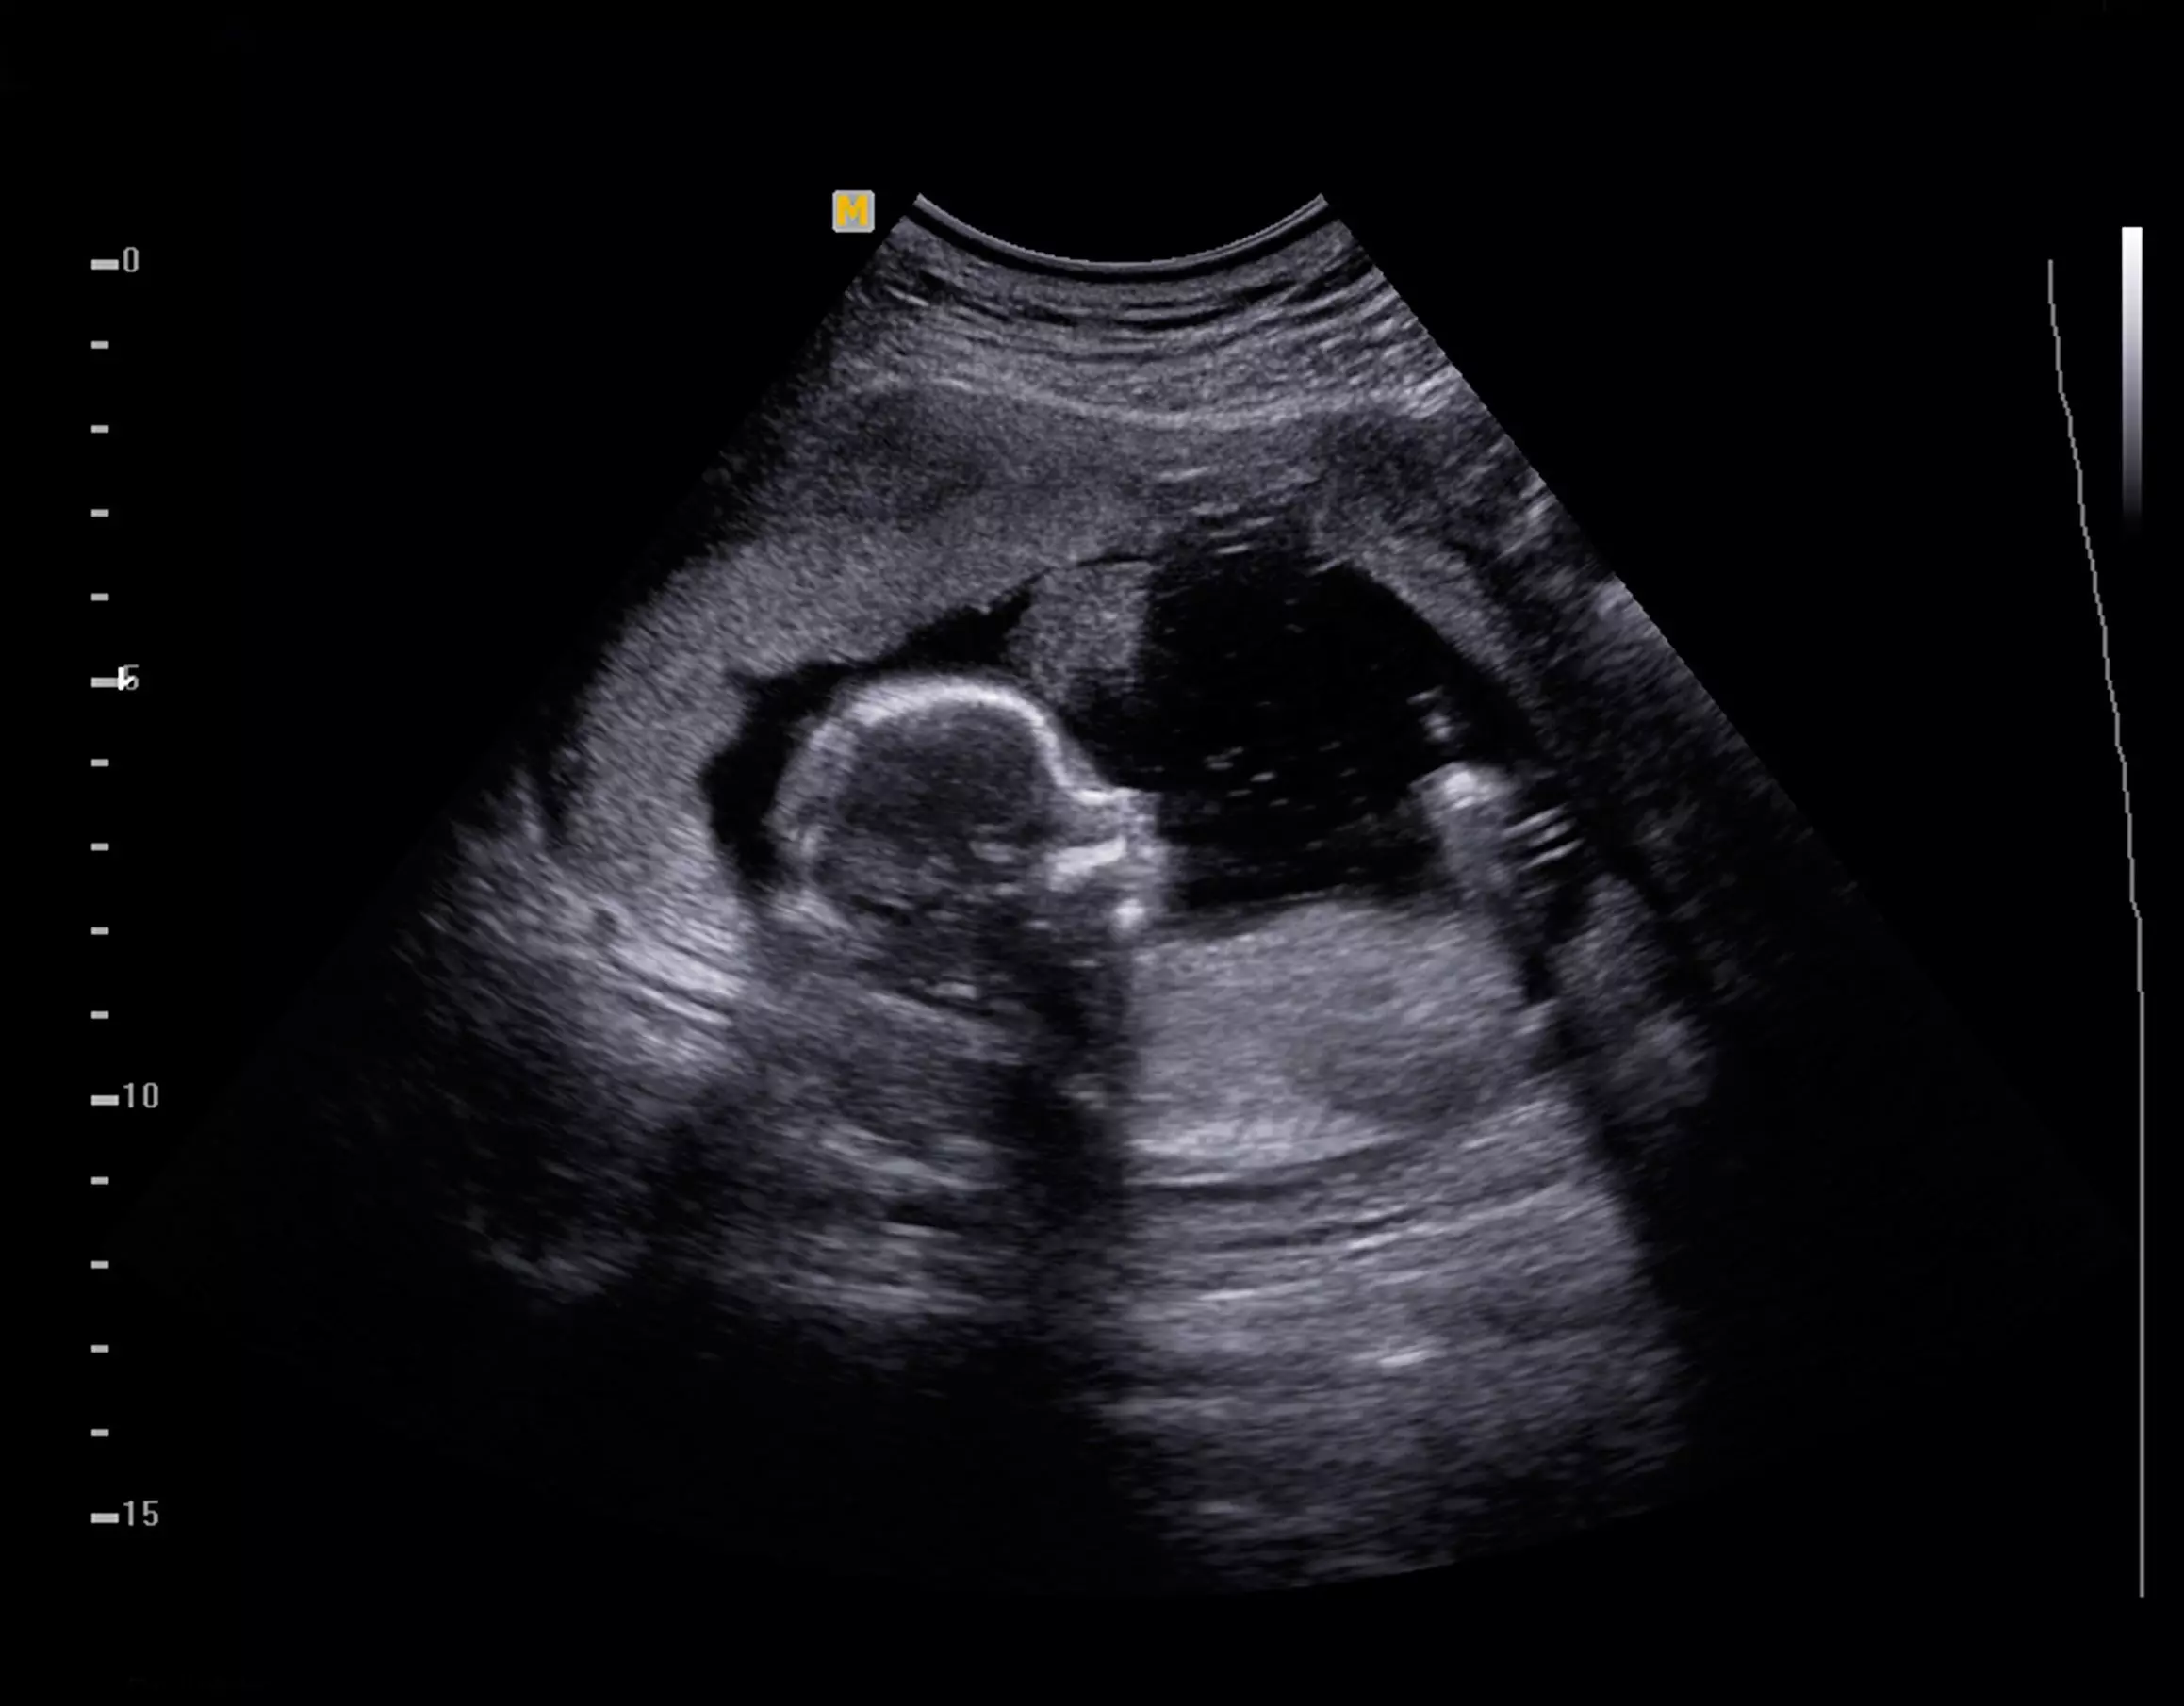

In 1996, when Tom Glessner of National Institute of Family and Life Advocates (NIFLA) began talking to me about taking the center I served into the medical realm, I was yet to grasp the enormity of the concept. Still, when we introduced the idea to our supporters we announced our change by saying, “What if a woman could actually see her child before making a pregnancy decision?”

As more and more pregnancy help centers added ultrasound, the tone in our movement shifted dramatically. Our interactions with clients and patients became less confrontational and more relational. We realize now that our strength is in, “Come and See.”

Today, abortion businesses are closing. There are various reasons for this, but one is that “Come and See” is so effective. Yes, there is a long way to go. And yes, we still have chemical abortions occurring at an alarming rate. But . . . “Come and See” will soon—if not already—impact this area of the abortion industry, too.